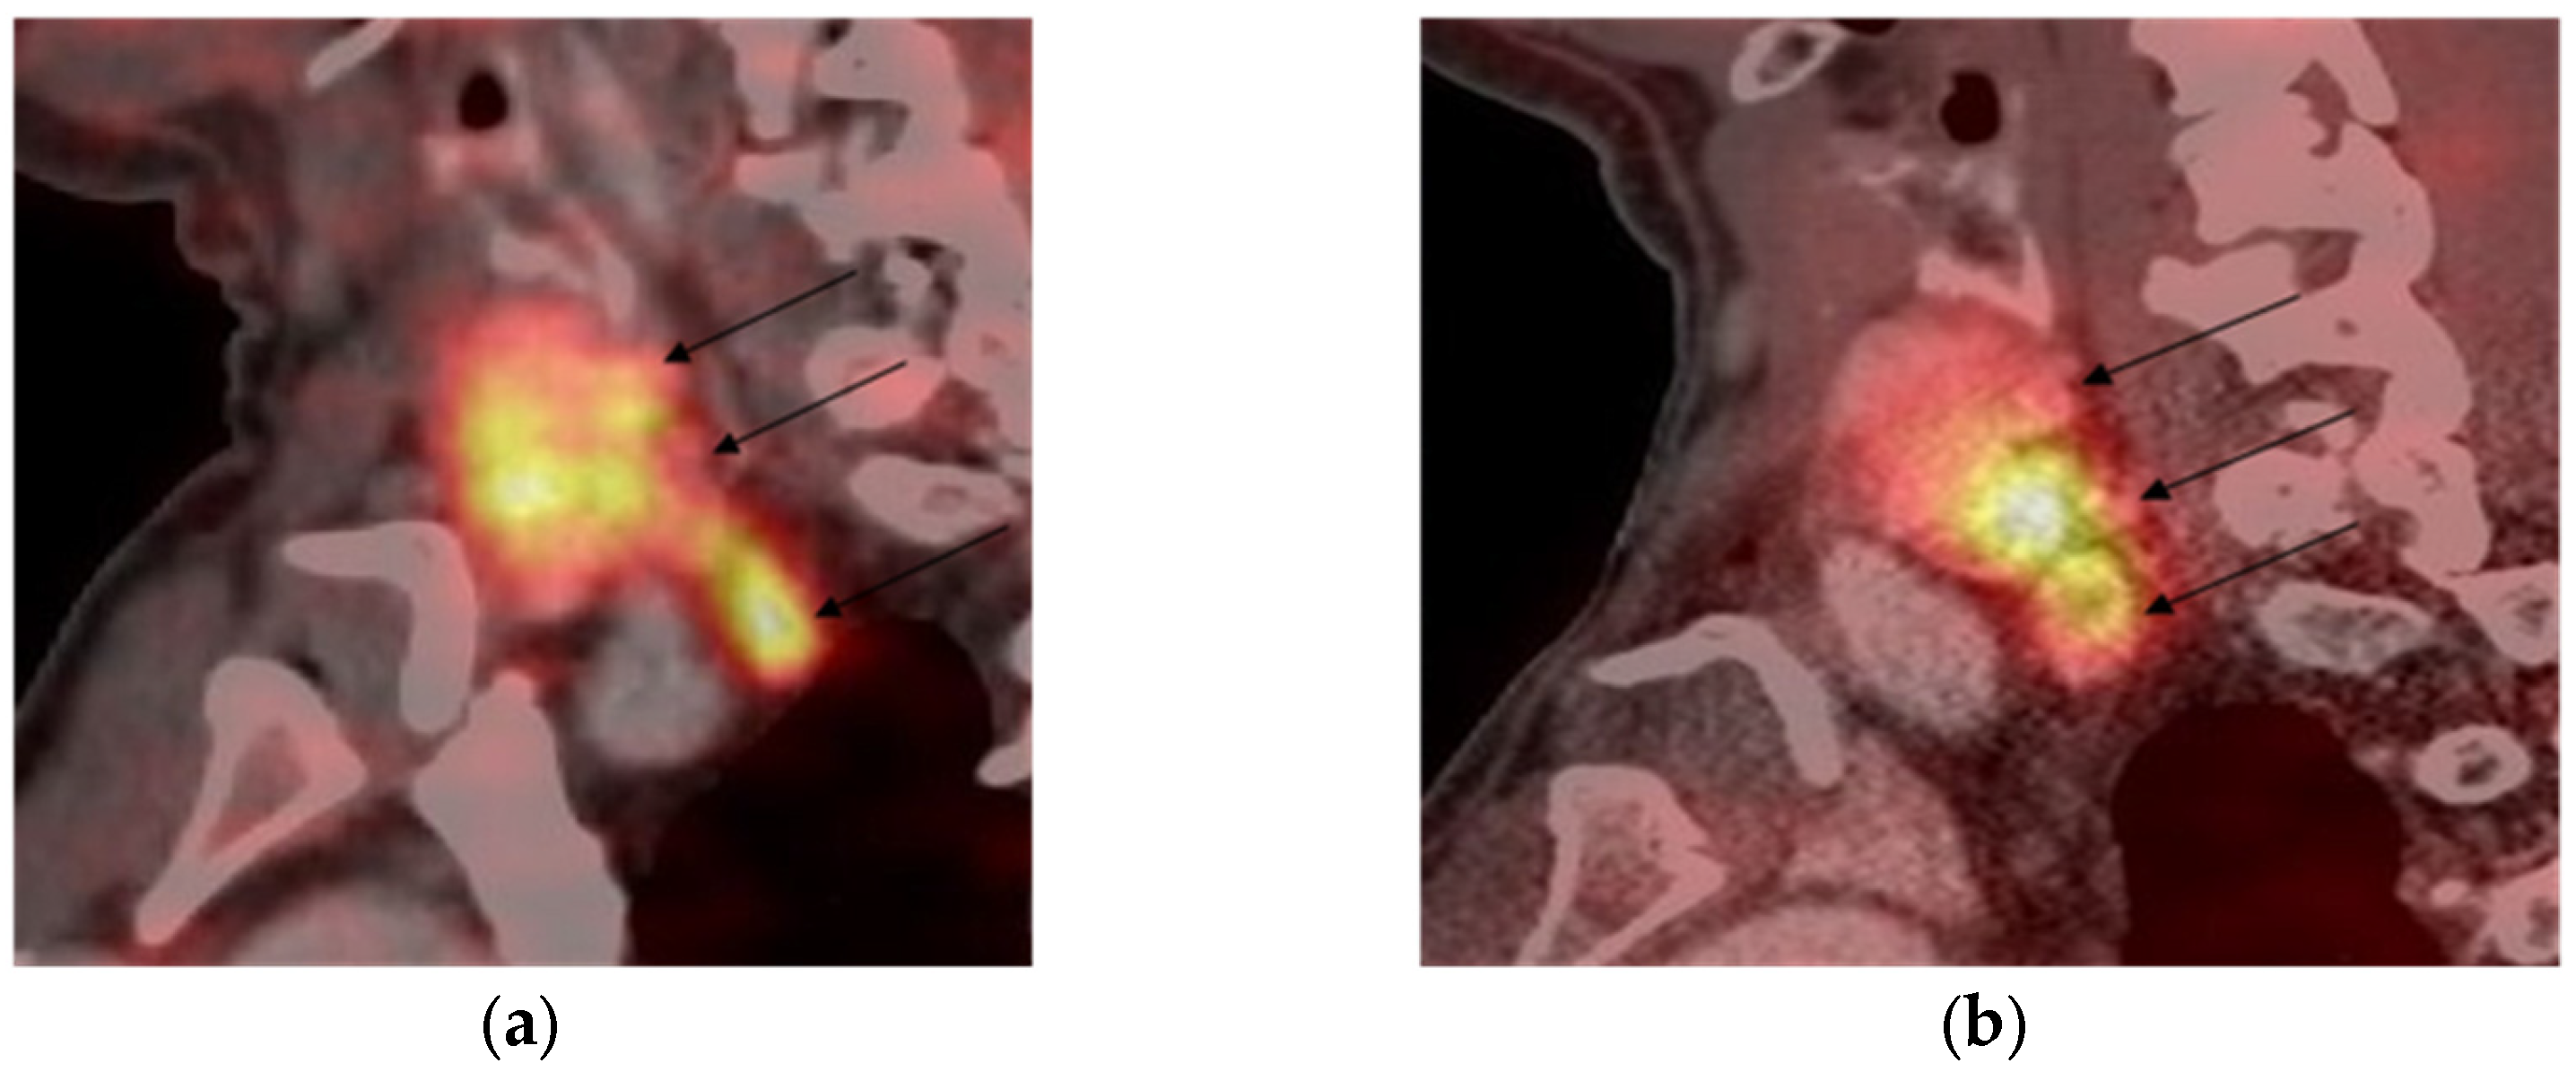

3.2. [68Ga]-DOTA-Peptide PET/CT Results